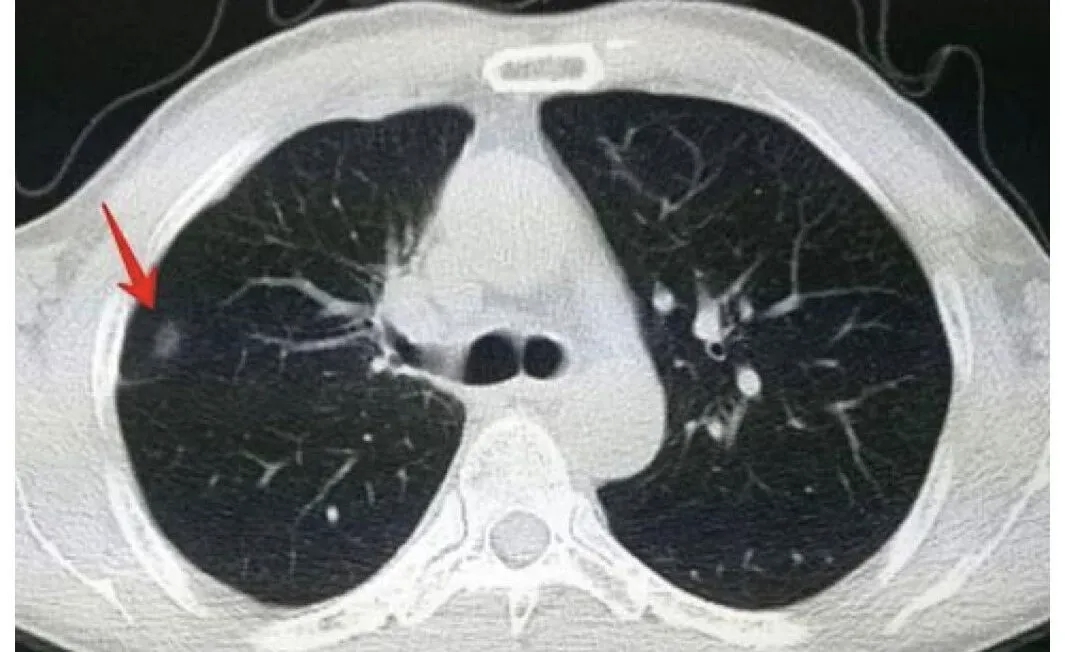

随着体检CT的普及,越来越多人发现肺结节。今天我们就用最通俗的语言,完整解读肺腺癌从最早期到进展期的全过程,帮助您理解体检报告上的专业术语。一、肺腺癌发展的四个阶段 1.不典型腺瘤样增生(AAH)-"预备期"性质:肺里的几个"调皮细胞",还没达到癌症标准特点: 直径通常≤5mm CT显示为纯磨玻璃结节(像一小片薄雾) 生长非常缓慢,可能多年不变处理建议:每年做一次CT复查即可2.原位腺癌(AIS)-"笼中虎"性质:最早的癌症,但被完全"困住"关键特征: 癌细胞局限在原位,未突破基底膜 CT表现为边界清晰的纯磨玻璃影 发展缓慢,有的几年都不变化 手术切除后治愈率接近100% 不需要化疗放疗处理原则: ≤8mm:可以继续观察 >8mm:可能需要手术切除3.微浸润腺癌(MIA)-"初露锋芒"性质:癌细胞刚"伸出爪子"(浸润≤5mm)特点: 已突破基底膜,但破坏范围很小 CT显示磨玻璃中出现小实性成分 不会发生转移处理原则: 建议手术切除 治愈率高达98% 通常不需后续治疗4.浸润性腺癌(IAC)-"危险分子"性质:癌细胞开始"大举进攻"危险特征: 浸润范围>5mm CT显示不规则实性结节,可能有毛刺、分叶 可能会发生转移(骨、脑、肝等)处理原则: 需要尽快手术 可能需配合化疗/靶向/免疫等治疗 预后与发现早晚密切相关二、重要知识补充1.发展规律: 不典型腺瘤样增生→原位腺癌→微浸润腺癌→浸润性腺癌→转移 (这是一个渐进过程,但不是必然的过程,并非所有结节都会发展)2.观察与手术的平衡: <8mm的纯磨玻璃结节:可以安全观察 ≥8mm或实性成分增加:考虑手术 微浸润阶段是最佳手术时机3.特别提醒: 定期复查最关键 具体治疗方案必须咨询专业医生三、常见疑问解答Q:查出肺结节就是得肺癌了吗?A:不是!大多数肺结节都是良性的,需要专业医生评估。Q:磨玻璃结节危险吗?A:纯磨玻璃结节多为良性或极早期病变,但要定期复查。Q:需要立即手术吗?A:不一定,要结合大小、变化速度等综合判断。记住:早发现、早诊断、早治疗是关键!发现肺结节不必过度恐慌,但一定要重视定期复查。